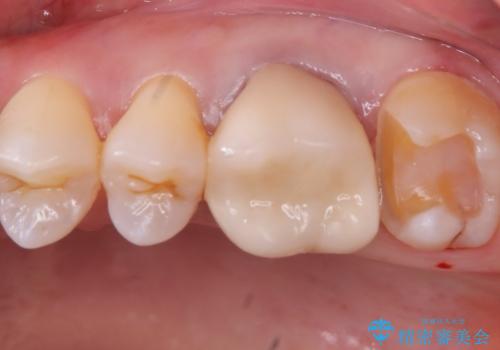

- 主訴:昔入れた銀の詰め物を白い物に替えて金属を無くしたい。

審美性、適合性の観点からセラミックインレーでのやり替えとなりました。

保険適用のメタルインレーを除去した際、下に広がっているカリエスも除去し形成印象を行いました。